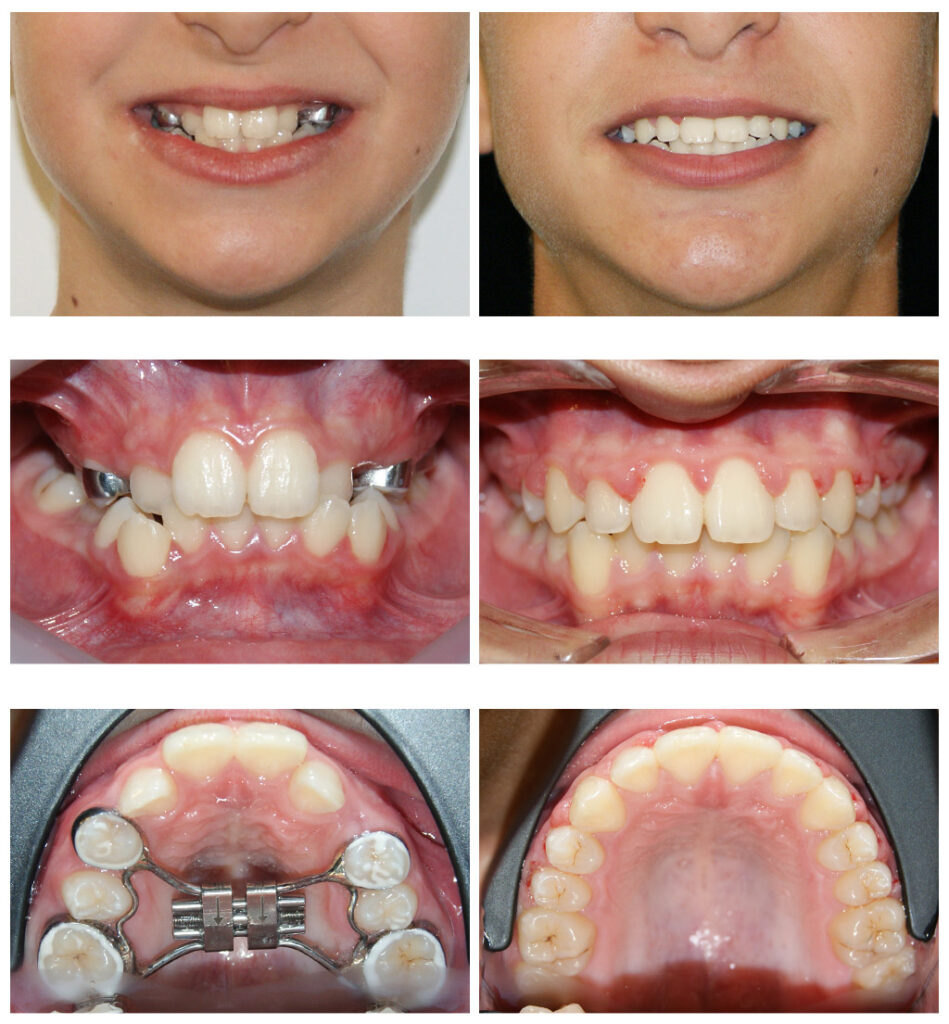

Corectarea muscaturii inverse cu forte extraorale – masca Delaire și disjunctor maxilar. Câteva luni pentru rezultate de care copilul se bucură întreaga viată

Corectarea muscaturii inverse cu forte extraorale – masca Delaire și disjunctor maxilar Alegem aparatul potrivit la vârsta potrivită